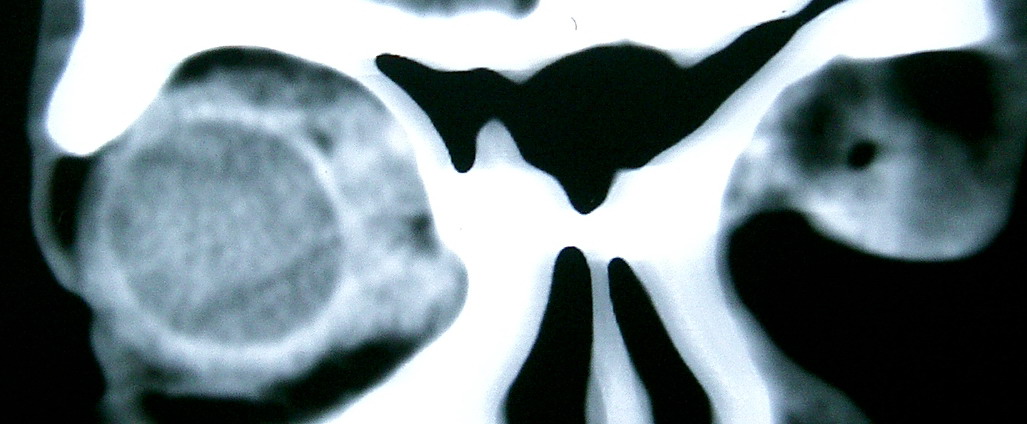

眼眶冠扫,平扫CT:

左眼球内上方可见不规则软组织块影,大小约2.5*1.0CM,与邻近组织分界不清,相邻之内直肌、上直肌增粗,眼环正常,眶壁骨质无破坏,左上颌窦底部可见粘膜增厚,其余副鼻窦未见异常。

IMP:1,左眼眶肿物;2,左上颌窦炎